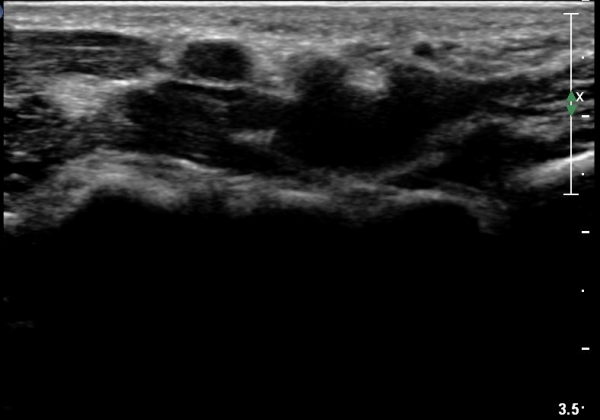

¼ö±Ù°ü ±ÙÀ§ºÎ Ⱦ´Ü¸é°Ë»ç¿¡¼­ Á¤Á߽ŰæÀÇ ºÎÁ¾ µî ƯÀÌ ¼Ò°ßÀÌ º¸ÀÌÁö ¾Ê´Â´Ù(»çÁø 2).